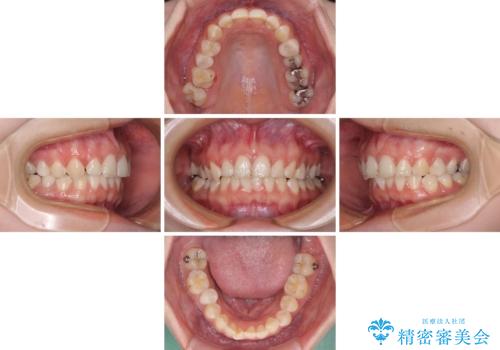

- 前歯の歯列不正を気にして来院された患者様です。

インビザラインでの矯正治療を希望されていましたが、奥歯の咬み合わせがインビザライン単独では改善困難と判断されたので、補助装置を併用することとしました。

まずは裏側の装置やワイヤー矯正を用いて歯列幅の狭い上顎を側方に拡大しつつ全体を後方に移動させ、その後インビザラインにて歯列を整えることとしました。

奥歯の咬み合わせの改善は、インビザライン単独では達成しきれないことがあるため、ワイヤー矯正などの補助装置を併用する場合があります。

インビザライン単独の場合と比べ、治療結果は大きく異なります。